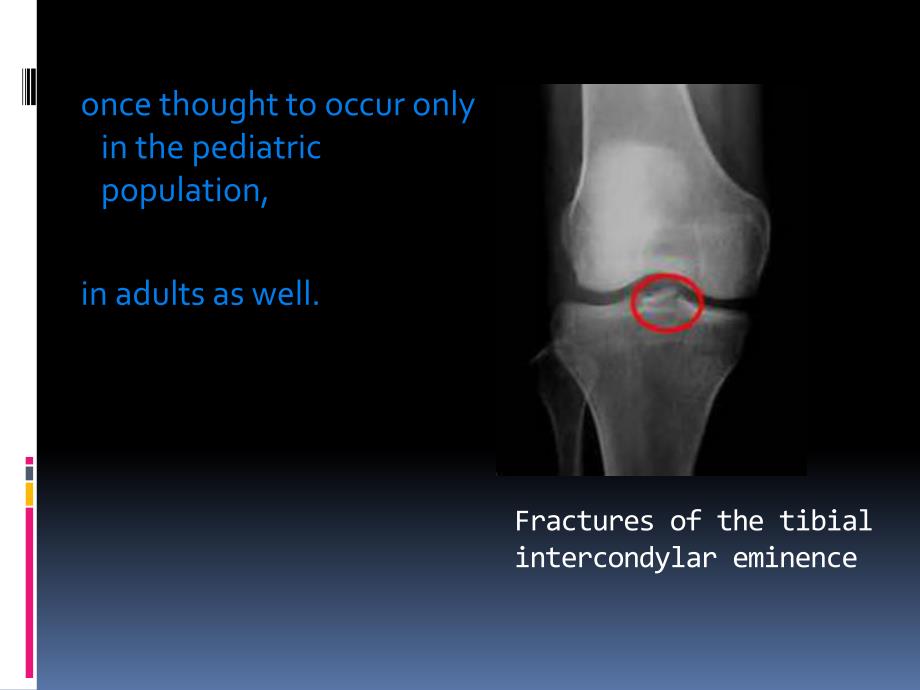

1、Arthroscopic Reduction and Internal Fixation of TibialEminence Fractures once thought to occur only in the pediatric population,in adults as well.Fractures of the tibial intercondylar eminence The ability to arthroscopically 1.evaluate the fracture pattern 2.address concomitant intraarticular pathol